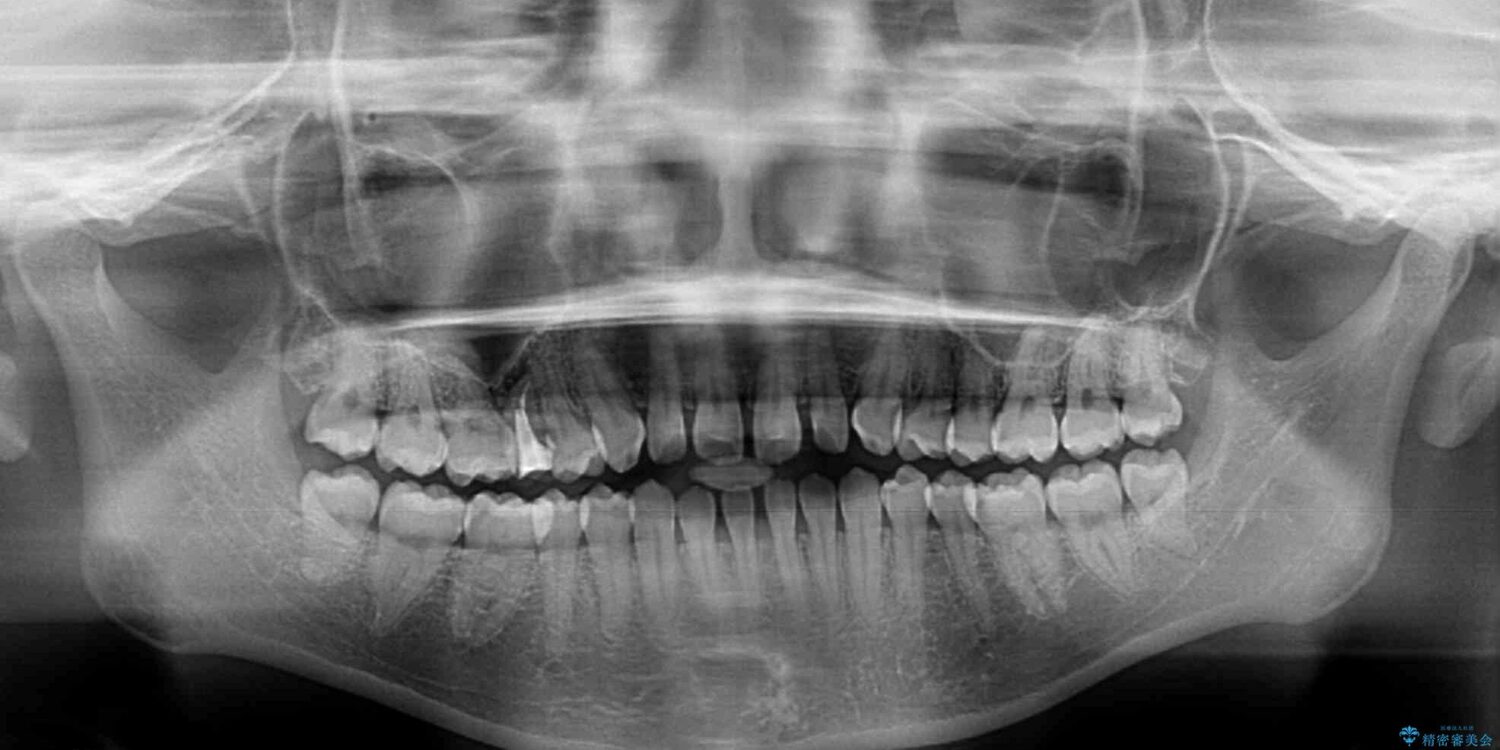

治療前

• 隙間だらけの歯列 インビザラインで改善 治療前画像